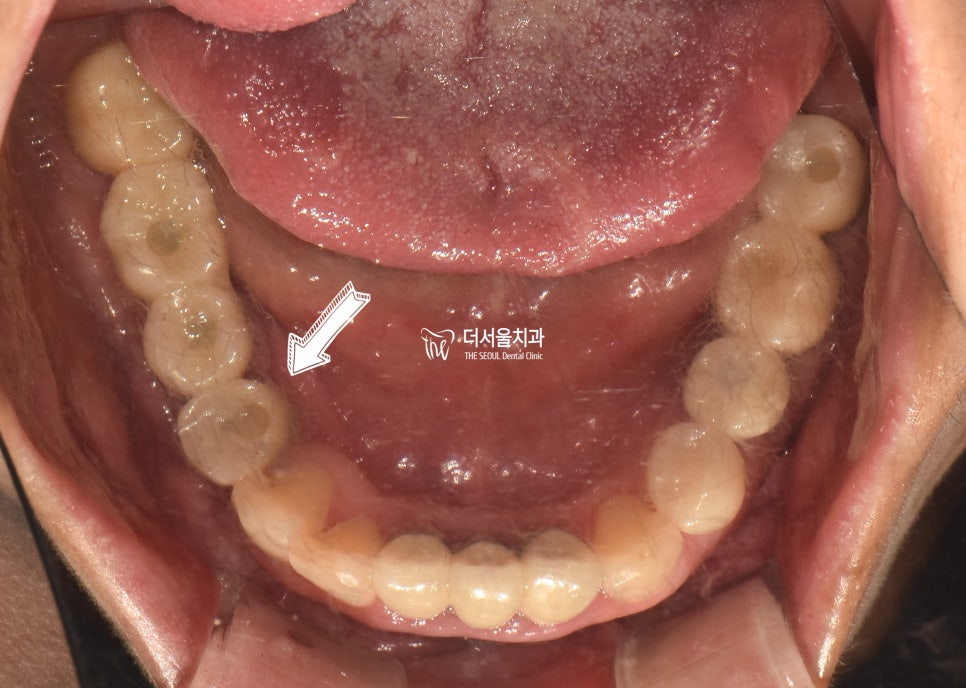

골 유착하는 시간을 가져주고

최종 보철을 수복했습니다.

자연치와 유사하고 튼튼한

지르코니아 크라운을 씌워드렸습니다.

옆 치아와 이질감 없이

자연스러운 모습을 보여주는데요.